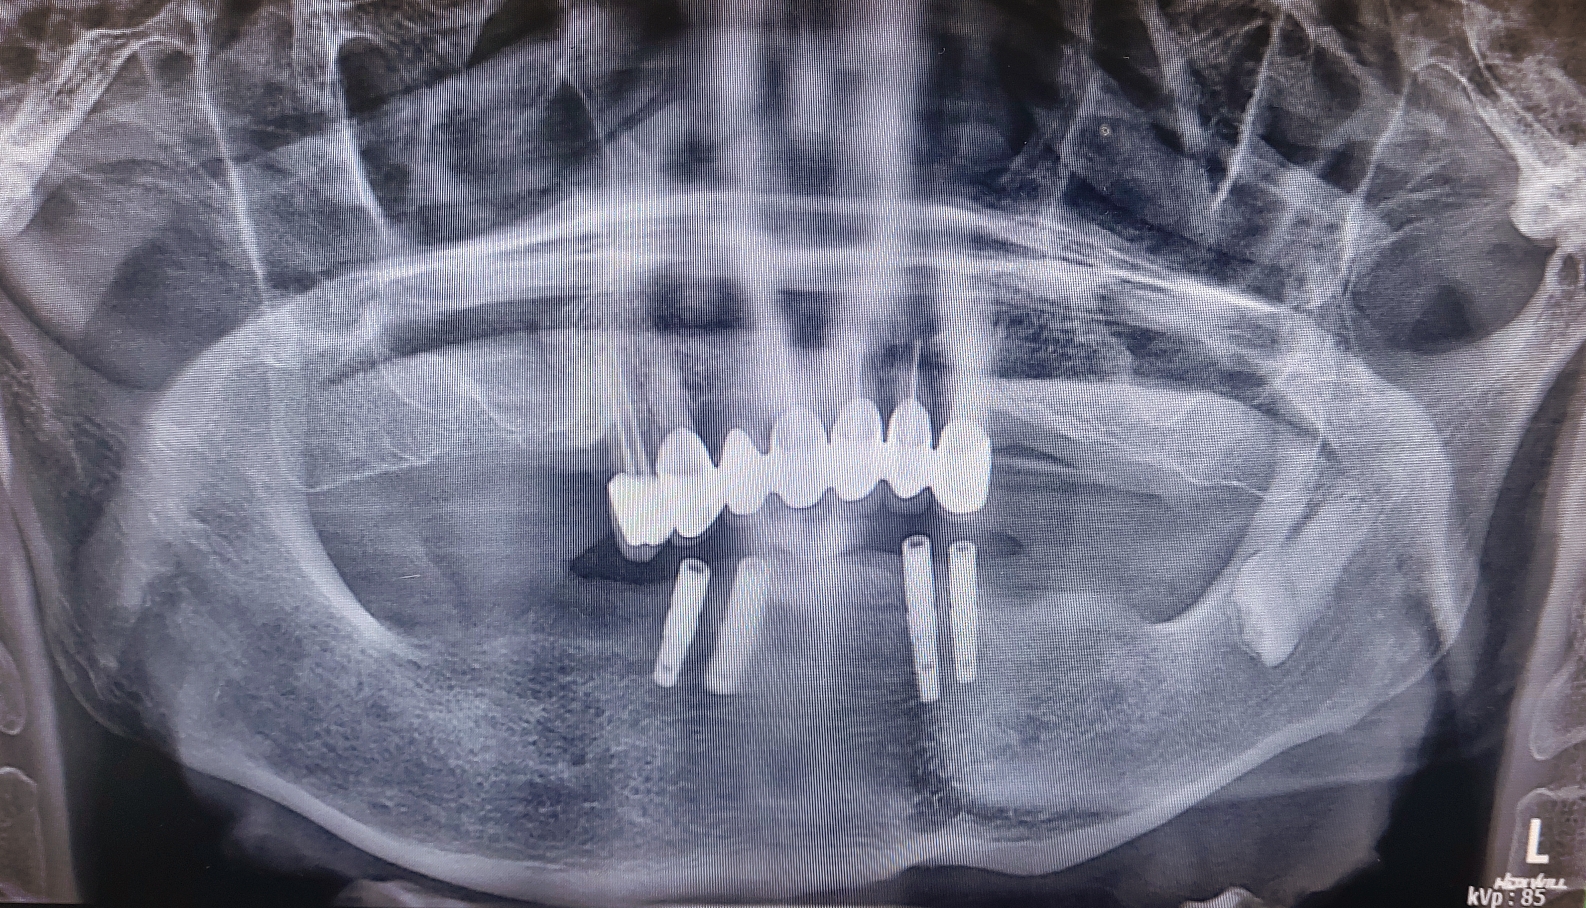

임상에서 하악의 치아가 전부 없는 경우 임플란트를 2개 에서 4개 정도 사용하여 임플란트 고정성 틀니는 아주 많은 환자분들이 선택하는 치료 옵션중 가장 보편적인 치료중 하나입니다.

제가 CT를 찍고 환자분께 일주일만 시간을 주시면 일주일뒤에는 예쁜 고정성 치아로 만들어 드린다고 자신있게 약속을 드린 환자분이었습니다.

심지어 임플란트를 단 4개만 심더라도 고정성으로 해드릴려고 노력하고 있습니다. 환자분이 느끼시는 만족도가 너무 차이가 납니다. 예전에는 교합력만으로 그 만족도를 가늠할려고 하였지만 그 와는 별개로 틀니를 빼고 있는 밤시간에 느끼는 무치악 스트레스도 무시 못하는 요인이라고 생각이 됩니다.

당장 비용 문제로 크게 고민 되시는 분이 아니라면 웬만하면 하악에서는 특히 고정성 치료를 권해 드리고 있습니다. 그리고 비용도 아예 일정금액으로 고정 시키고 심는 갯수는 제가 최대한 많이 식립해 드릴려고 하고 있습니다.